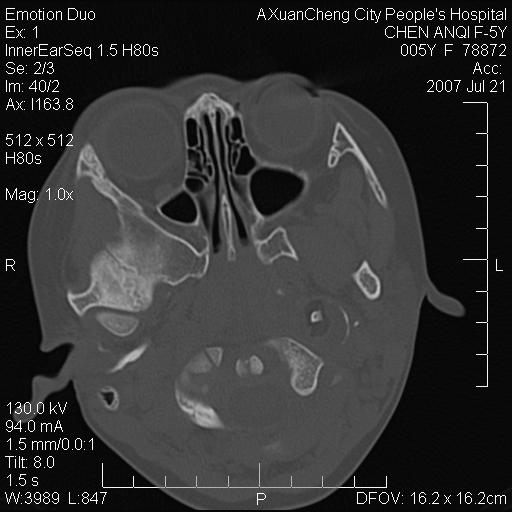

标题: PED0273:5岁,左耳流脓痛疼一周,颅底骨质破坏 [打印本页]

标题: PED0273:5岁,左耳流脓痛疼一周,颅底骨质破坏

患儿5岁,左耳流脓痛疼一周,左外耳道肉芽组织填塞 软组织窗显示病灶内结节状低密度影为气体密度

左侧中耳炎并胆脂瘤,左颞骨岩部骨质破坏并颅内感染积气。

考虑化脓性中耳乳突炎伴胆脂肪瘤形成并左颞叶感染,不除外合并嗜酸性肉芽肿.